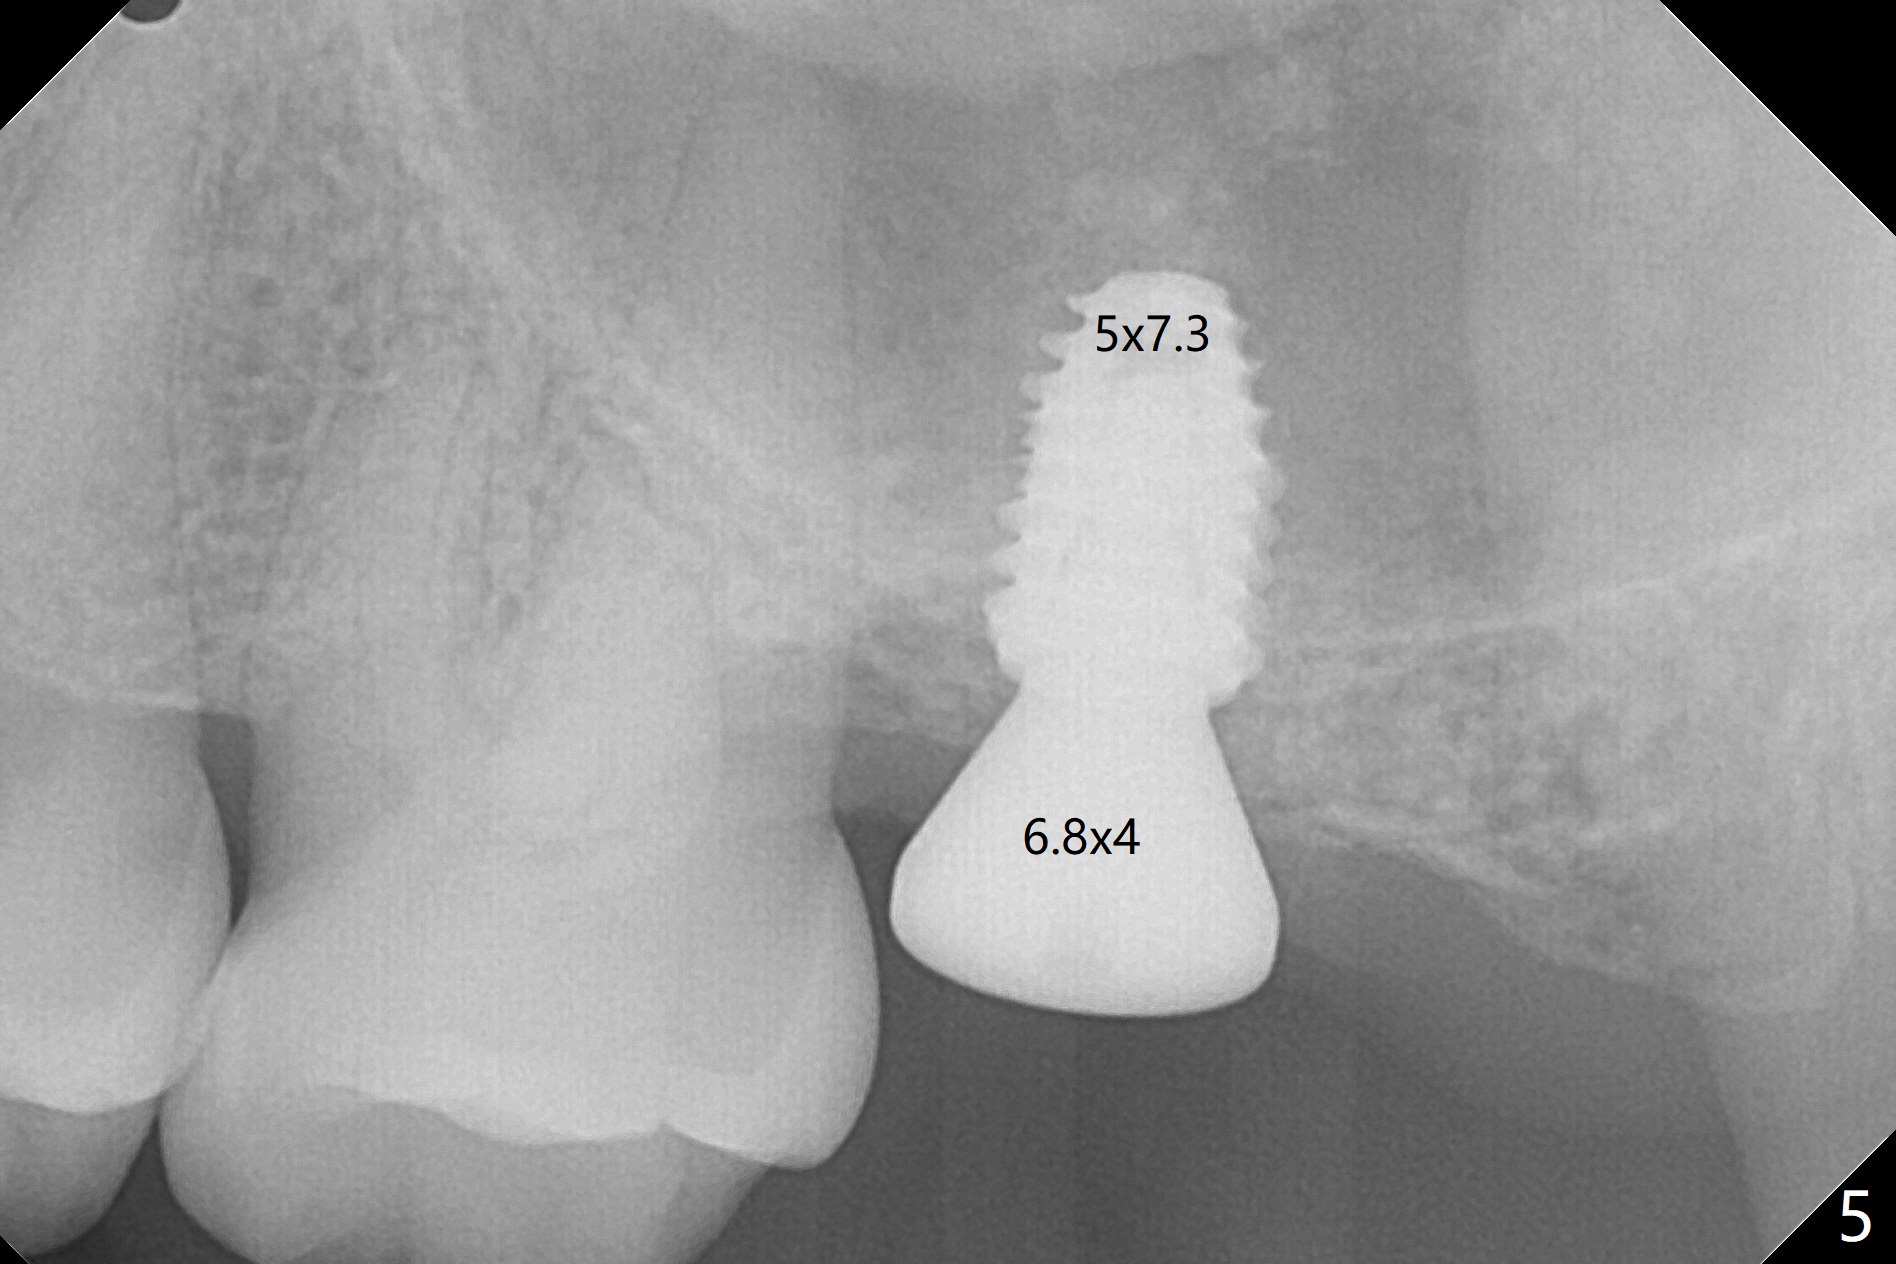

After 4.5x7.3 mm drill with 3 O-rings at #15, use 2.2x7.3 mm one with 2 O-rings. The sinus floor feels like to be perforated, but perio probe does not find the perforation. Nose blowing does not reveal air leakage. It seems fine when 3.0x7.3 mm one with 2 O-rings is being used. The sinus membrane perforates when Magic Sinus Lifter is used. Mixture of autogenous bone (from drills) and allograft does not stick to the periosteal elevator (Fig.1). Forty-minute centrifuge leads to separation of serum (Fig.2 S) from Red Blood Cell layer (R). The separation of the top tube is incomplete with RBC invade the serum layer in a few second (Fig.3 arrow). While the serum layer of the bottom tube is prepared for PRF membrane, a part of the serum layer of the top tube is withdrawn to make sticky bone (Fig.4). The top tube returns to the centrifuge for another 30 minutes to make the second PRF membrane. The first PRF membrane is inserted into the osteotomy and pushed into the sinus with empty feeling, followed by the sticky bone and last by the 2nd PRF membrane. A 5x7.3 mm implant is placed with ~ 10 Ncm, followed by a 6.8x4 mm healing abutment (Fig.5,6 (retrospectively healing screw should be used to reduce sinus-oral communication)). There is no mushroom in the sinus, but hopefully the sticky bone will stick to the bottom of the sinus for maturation. Sinus surgery precaution is provided. Next time tap or dummy implant will be used for sinus lift after initial osteotomy with guide. In fact the patient with diabetes under control has mild cold. The procedure should have been canceled. There is no postop nasal hemorrhage or discharge. The patient returns nearly 8 months postop. The wound is infected. The healing abutment is changed to a healing screw with oral antibiotic. Two weeks later, the area remains infected with symptoms (Fig.7-9). The healing screw is not covered completely. After implant removal, the sinus membrane is perforated. A piece of collagen plug (preferably Osteogen plug) is inserted (Fig.10,11). Because of the concavity, bone graft seems necessary when the wound heals. One week later, perimplantitis develops at #2. The patient is ready for the 3rd placement 1 year 5 months post last implant removal (Fig.12). The bone is 1.8 mm thick, apparently composing of 2 fused cortical plates. Make an incision for both external and internal sinus lift with retraction. Find the old guide to start osteotomy including bone trimmers and use Magic Lifter. If the membrane is broken, open the lateral window to repair with PRF.